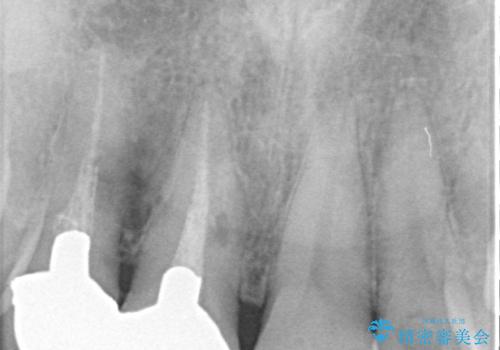

下顎の歯列は整えたいというご希望とは別に、上顎前歯にうずくような痛みや違和感があるとのことで、先に根管治療や歯根端切除術を行うこととしました。

痛みが消えた後に、より目立たない装置をご希望とのことで、下顎前歯の舌側矯正で部分矯正を行い、歯列が整い、上顎前歯歯根部の病変が消退したことを確認した上で、上顎前歯をオールセラミッククラウンにて補綴治療を行うこととしました。